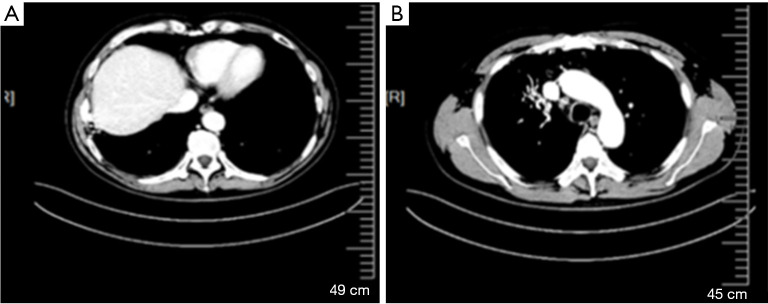

Case description: In this case, we present a 58-year-old male with metastatic pulmonary adenocarcinoma (ADC) who had an EGFR exon 19 mutation and received first-line gefitinib and second-line osimertinib. Biopsy results from different progressive sites confirmed the presence of SCLC in pleural metastatic specimens, while the primary tumor had the EGFR exon 19 mutation and mutations ofPhosphatidylinositol-4,5-bisphosphate 3-kinase catalytic subunit alpha (PIK3CA) andv-Ki-ras2-Kirsten rat sarcoma viral oncogene homolog (KRAS). We utilized an effective combination therapy of permanent radioactive iodine-125 seed implantation (PRISI) as local consolidative therapy (LCT), along with the standard carboplatin-etoposide regimen for SCLC and continued osimertinib. Extracranial tumors were successfully controlled. The patient succumbed to intracranial disease progression without radiotherapy, with an overall survival (OS) of 15 months after SCLC transformation.